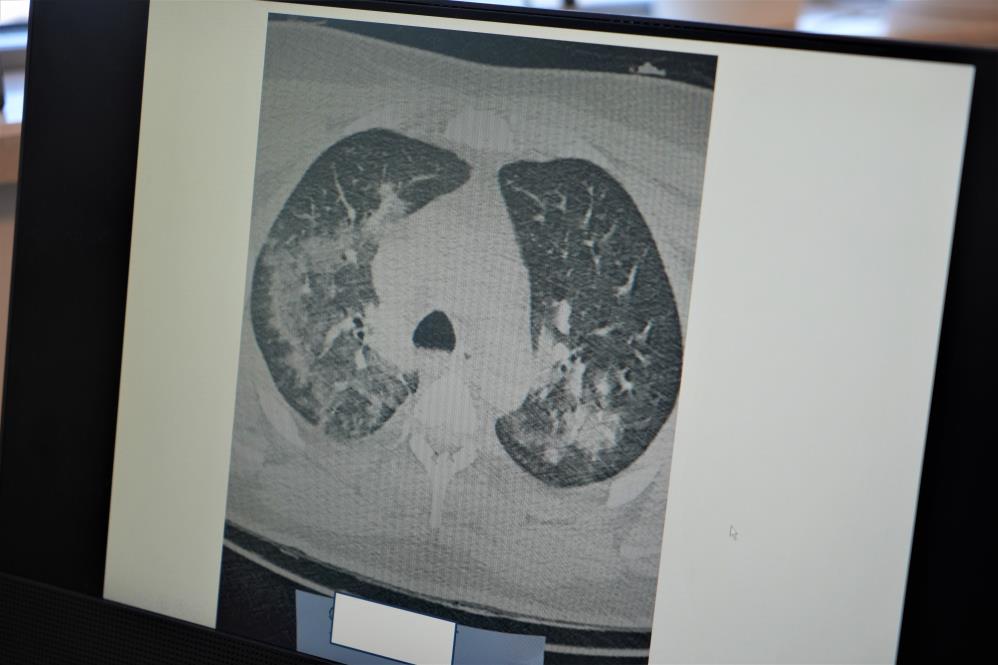

Kovid-19'un damarlarda bıraktığı hasarın önemine dikkat çeken Prof. Dr. Özkaya, "Kovid-19'u yaşadıktan sonra koronanın vücudumuza ne yaptığını öğrendik. Özellikle Kovid-19'dan sonra gerçekten kalp, akciğer ve bütün vücudumuzdaki kılcal damalarımızda hasar oluştu. Bu Kovid-19'un yüküne bağlı olarak sitokin fırtınası dediğimiz bir tablo olan kanın içindeki kan hücreleri taşıyan plazmamızı, kan öz sıvısı öyle tahrip edici hale getirdi ki, damar duvarındaki yapıyı değiştirdi ve bozulmalara neden oldu. Bu durumda pandemi öncesi döneme göre artık damarlarınız da kalıcı hasarlar olabilir. Yaptığınız ağır sporları; halı saha maçı, ağır bisiklet sporları, ağır yüzmeleri pandemi öncesine göre vücudunuz bunları kaldıramayabilir. Hayatı tehdit edici sonuçlar doğurabilir. Ağır sporlar sonrası kalbinizin ve akciğerlerinizin kanını vücudunuz damar hasarı nedeniyle yeterince sağlayamazsa kalp krizleri ve kalp yetmezlikleri ile karşılaşabilirsiniz. Kovid-19 sonrası virüs yükünüze bağlı olarak ortaya çıkan damar duvarındaki değişiklikler kan akımını etkilediği için ağır sporlar sonrası kalp krizleri ve kalp yetmezliği ortaya çıkıyor" diye konuştu.

"Damar embolisi dediğimiz bir tablo var. Bu durumda çok sık görülmeye başladı. Vücuttaki pıhtılaşma probleminin 3 ana sebebi vardır. Birincisi damar duvarı hasarı, ikincisi hareketsiz yaşam, üçüncüsü de genetik yatkınlıktır. Kovid gerçekten pıhtılaşmaya yatkınlık yapan damar duvarı hasarını yaptı. İkinci olan hareketsizlik ise uzun seyahatler, hastalık nedeniyle evde yatmalar sonucu pıhtılaşma oluyor ve buda akciğerlerde damar tıkanıklığına neden oluyor. Bu durum ise ölüme kadar götürüyor. Özellikle sıcak hava ve nemli havalarda ağır sporlarınızı yaparken dikkatli olmanızı öneriyoruz. Gerçekten korona öncesine göre yaptığınız ağır sporlar da vücudunuz sizin kan akışınızı yeterince sağlamayabilir. Uzun süre hareketsiz kalmamanızı öneriyoruz. Özellikle gençlerimizin bu 2 zıt durum olan hem ağır spor hem de hareketsiz yaşama dikkat etmelerini öneriyoruz."